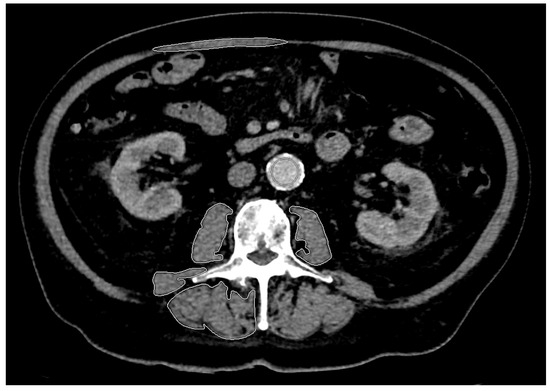

Purpose: Sarcopenia is considered a negative prognostic factor in patients with malignant tumors. Among other diagnostic options, computed tomography (CT), which is repeatedly performed on tumor patients, can be of further benefit. The present study aims to establish a framework for classifying the impact of sarcopenia on the prognosis of patients diagnosed with esophageal or gastric cancer. Additionally, it explores the significance of CT radiomics in both diagnostic and prognostic methodologies. Materials and Methods: CT scans of 83 patients with esophageal or gastric cancer taken at the time of diagnosis and during a follow-up period of one year were evaluated retrospectively. A total of 330 CT scans were analyzed. Seventy three of these patients received operative tumor resection after neoadjuvant chemotherapy, and 74% of the patients were male. The mean age was 64 years (31–83 years). Three time points (t) were defined as a basis for the statistical analysis in order to structure the course of the disease: t1 = initial diagnosis, t2 = following (neoadjuvant) chemotherapy and t3 = end of the first year after surgery in the “surgery” group or end of the first year after chemotherapy. Sarcopenia was determined using the psoas muscle index (PMI). The additional analysis included the analysis of selected radiomic features of the psoas major, quadratus lumborum, and erector spinae muscles at the L3 level. Disease progression was monitored according to the response evaluation criteria in solid tumors (RECIST 1.1). CT scans and radiomics were used to assess the likelihood of tumor progression and their correlation to sarcopenia. For machine learning, the established algorithms decision tree (DT), K-nearest neighbor (KNN), and random forest (RF) were applied. To evaluate the performance of each model, a 10-fold cross-validation as well as a calculation of Accuracy and Area Under the Curve (AUC) was used. Results: During the observation period of the study, there was a significant decrease in PMI. This was most evident in patients with surgical therapy in the comparison between diagnosis and after both neoadjuvant therapy and surgery (each p < 0.001). Tumor progression (PD) was not observed significantly more often in the patients with sarcopenia compared to those without sarcopenia at any time point (p = 0.277 to p = 0.465). On average, PD occurred after 271.69 ± 104.20 days. The time from initial diagnosis to PD in patients “with sarcopenia” was not significantly shorter than in patients “without sarcopenia” at any of the time points (p = 0.521 to p = 0.817). The CT radiomics of skeletal muscle could predict both sarcopenia and tumor progression, with the best results for the psoas major muscle using the RF algorithm. For the detection of sarcopenia, the Accuracy was 0.90 ± 0.03 and AUC was 0.96 ± 0.02. For the prediction of PD, the Accuracy was 0.88 ± 0.04 and the AUC was 0.93 ± 0.04. Conclusions: In the present study, the CT radiomics of skeletal muscle together with machine learning correlated with the presence of sarcopenia, and this can additionally assist in predicting disease progression. These features can be classified as promising alternatives to conventional methods, with great potential for further research and future clinical application. However, when sarcopenia was diagnosed with PMI, no significant correlation between sarcopenia and PD could be observed.